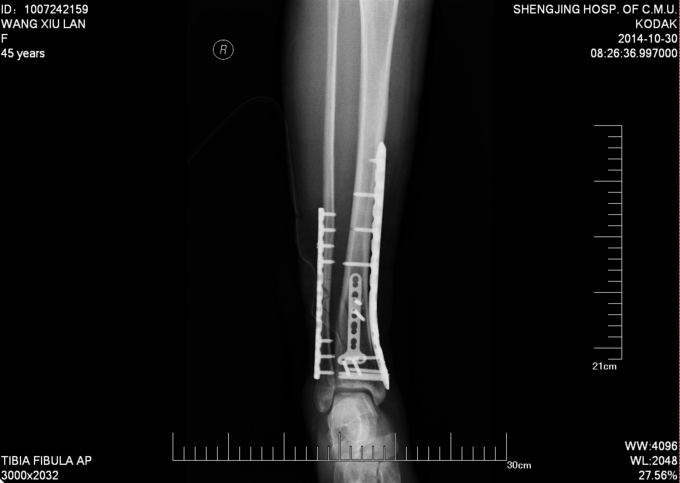

主诉:右小腿外伤后6天 现病史:患者2014-10-19日晚9时左右下楼时不慎摔倒,后于骨科医院就诊,行右下肢DR检查,提示右胫腓骨远端粉碎性骨折,后患者于骨科医院行夹板固定,并与当地祝家镇诊所输液治疗,具体治疗方案不详。后患者为求进一步诊治逐来我院。并以右胫腓骨远端粉碎性骨折收入院。患者病来一般状态可,二便正常,饮食睡眠可。

右踝关节肿胀明显,皮下瘀斑。右踝关节局部压痛明显。右足趾屈背伸因为疼痛活动较弱。右足背动脉搏动良好,末梢血运良好。

诊断:右胫腓骨远端粉碎性骨折 患者为右plion骨折,入院后局部肿胀明显,给予患肢抬高,冷敷,消肿等对症治疗,密切观察患肢皮肤情况,带皮肤条件良好的情况下,约2周后行右三踝骨折切开复位钢板内固定术。